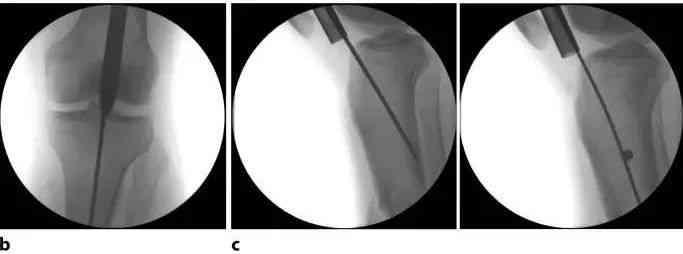

Рис. 9а. Открытие костномозговой полости из идеальной точки входа является критическим этапом хирургической процедуры. В переднезадней плоскости это медиальная часть латеральной большеберцовой шпоры. В латеральной плоскости правильная точка входа расположена на переходе между суставной поверхностью и передней корой головного мозга.

Рис. 9б. Правильное положение проводника — на одной линии с осью большеберцовой кости в передне-задней плоскости и как можно ближе к передней кортикальной поверхности в боковой проекции. Проводник имеет тенденцию перемещаться назад.

Рисунок 9c. В случаях, когда булавку или гвоздь невозможно вставить правильно, блокировка гвоздя или булавки помогает направить гвоздь в правильное положение.